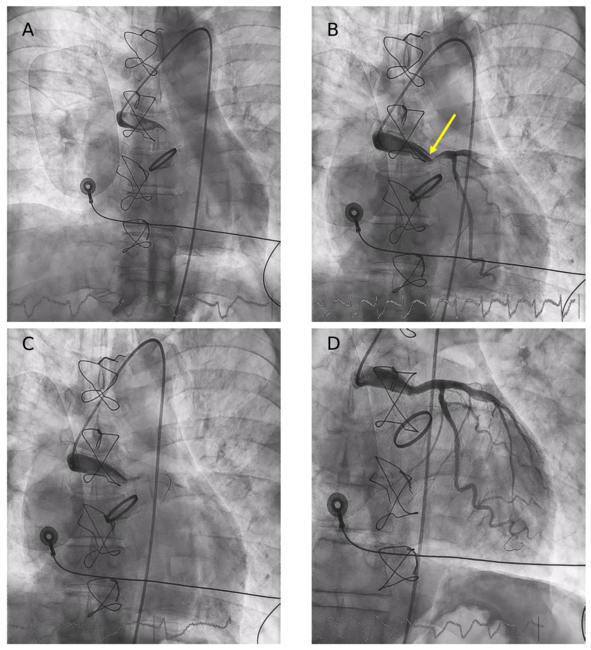

Very Late Thrombosis of a Hemi-Cabrol Coronary Graft: A Rare Cause of Cardiogenic Shock

Video Supplement to "Very Late Thrombosis of a Hemi-Cabrol Coronary Graft: A Rare Cause of Cardiogenic Shock" (Clinical Image).